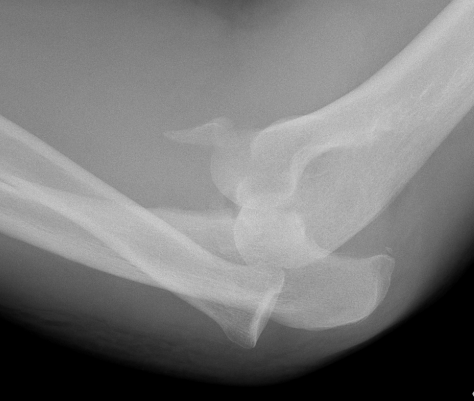

Complex Elbow Dislocation APComplex Elbow Dislocation Lateralelbo dis

Definition

Elbow dislocation with radial head fracture + coronoid fracture + MCL tear